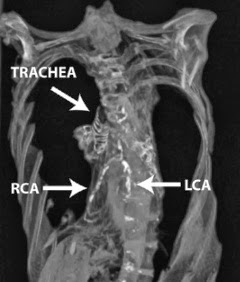

La calcificación de la derecha (RCA) y la izquierda (LCA) de las arterias coronarias aparece en color blanco en la tomografía computarizada (cortesía de la Sociedad Europea de Cardiología)

Los investigadores crearon las tomografías computarizadas de 52 momias egipcias en el Museo Nacional de Antigüedades en El Cairo (las momias no podían sustraerse, por lo que los análisis se realizaron en el museo). Podían ver las arterias en 44 de las momias. De estos, 20 tenían calcificación, un marcador de la aterosclerosis, en sus arterias, y en tres de las momias que la calcificación se puede ver en las arterias coronarias.

Las momias con signos de aterosclerosis tendían a ser aquellos que habían vivido el más largo, que promedian 45 años. Uno de los tres con enfermedad coronaria era la princesa Ahmose- Meryet - Amon, que vivió en Tebas alrededor de 1580-1530 a.C. y murió a los 40 años, y dos de sus tres arterias coronarias principales estaban bloqueadas. Si hubiera vivido hoy "habría necesitado una cirugía de bypass" dijo uno de los estudios de co-autores, Gregory Thomas, de la Universidad de California, Irvine. Ahora se conoce como la primera persona en la historia que han sufrido de la enfermedad coronaria.